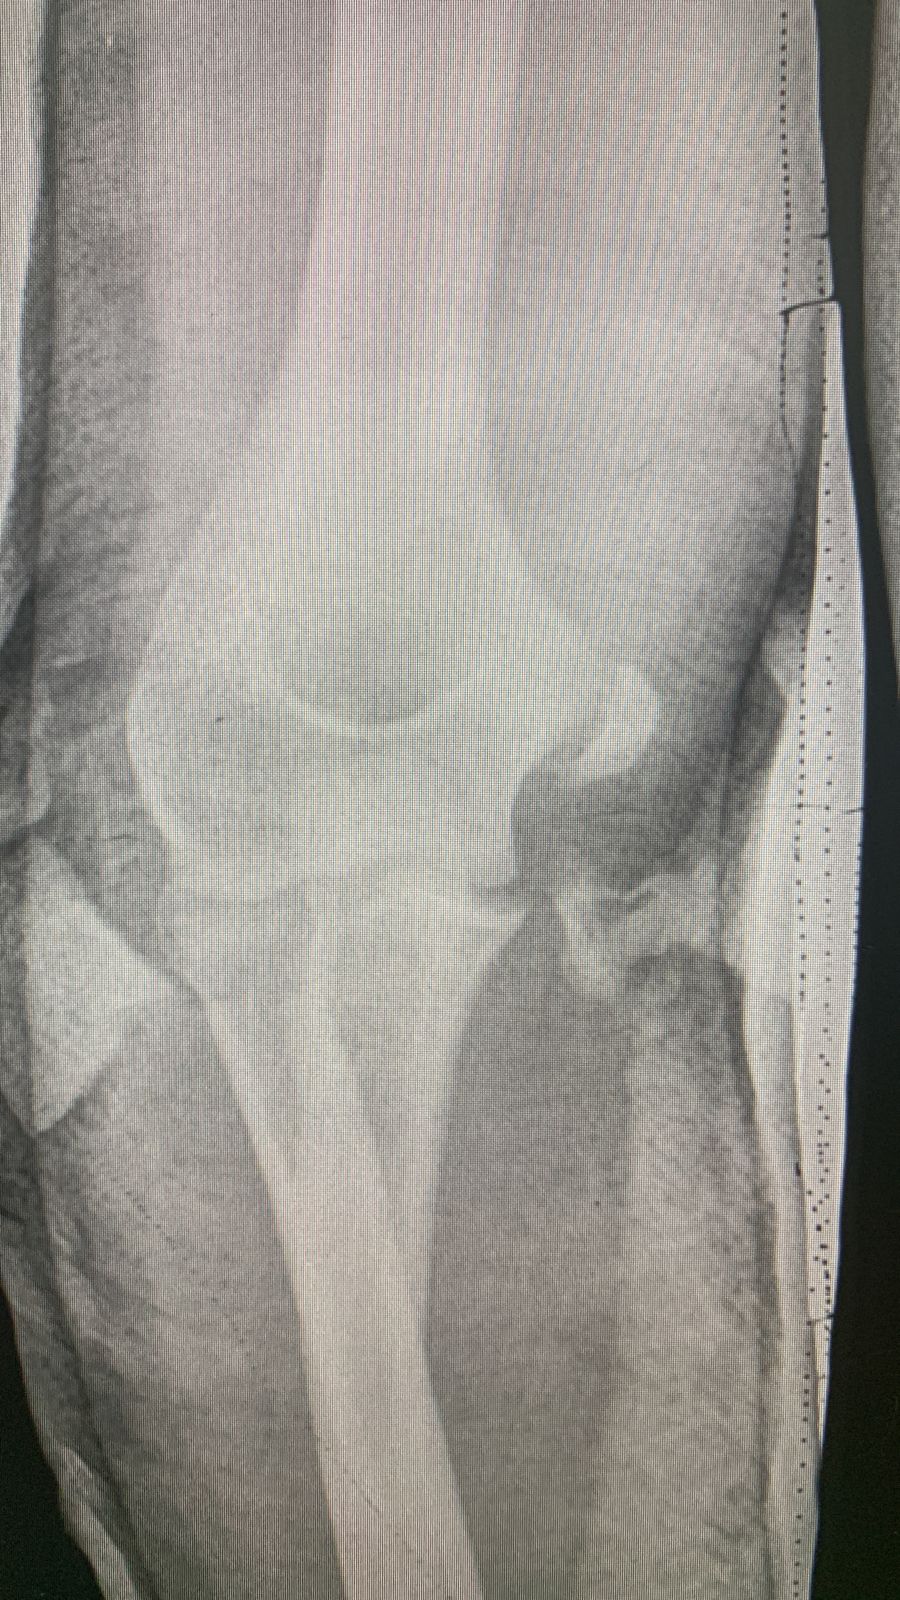

Перелом надмыщелка

Детская ортопедия Отправлено Антон 18 Июль 2022, 12:43

Месяц назад сломал вроде как медиальный надмыщелок,отходил в гипсе 1 месяц и неделю.

По итогу один врач говорит,что кость не срастается,но снял гипс.При всем при этом сказал,чтобы я разрабатывал руку и если за 2 месяца она не срастётся,то придётся убирать обломок.Другой же врач говорит,что туда не надо лезть,все должно зажить и также посоветовал разрабатывать.Кому верить и что делать?